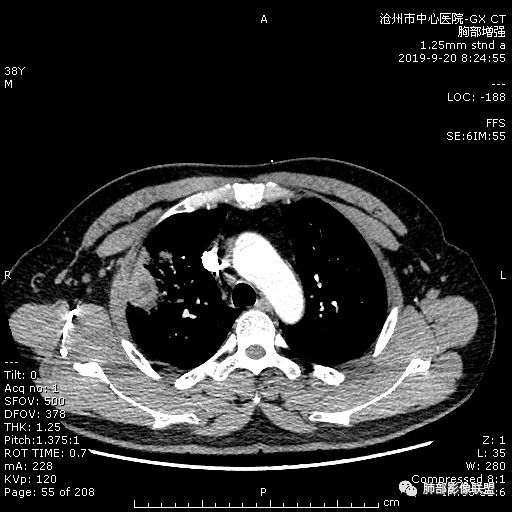

青年男性,肿瘤指标无异,右上中肺团片影,形态不规,跨叶生长,

病灶内见坏死,增强边缘强化,考虑炎性肉芽肿,TB,鉴别鳞。

年轻男性,咳嗽2月,痰中带血,胸痛,炎症指标稍高,肿标正常。影像,右肺上叶不规则团块影,浅分叶,伴边界不清磨玻璃影,从外周向内分布,局部胸膜增厚,病灶中央坏死,坏死边界尚清,空洞形成,空洞内壁光滑;考虑炎性肉芽肿性病变,结核可能,鉴别恶性肿瘤及真菌感染。病灶分布特点不考虑隐球。

右肺上叶不规则病灶,密度不均,有分叶,边缘不清,中央有坏死,坏死壁尚光滑,增强壁有强化,病灶有外朝内,整体收缩为主,慢性病程,考虑炎性病变,肺脓肿或者结核,淋巴结肿大,支气管截断,胸膜脂肪间隙变窄,加个鉴别恶性肿瘤。

近端支气管截断,非坏死区的强化特征,肺门区肿大淋巴结,所谓的“月牙铲”,这些强烈提示病变是癌;胸膜、相邻肋间肌的改变,提示是炎性改变;在癌与炎性肉芽肿之间,哪个占主导地位?是解决问题的关键;坏死区的形态,也支持炎性病变。

右肺上叶分叶状肿块(冠状位尤为明显),内见液化坏死,支气管截断,收缩力强,周围有片状影,右侧腋窝及纵隔淋巴结增大,增强有强化,定性恶性病变,脓肿形态及临床症状不符,暂排除。

右上肺占位,总体膨胀性生长,支气管截断,坏死明显,常规考虑鳞。

38岁,男性,慢性咳嗽2月,右胸痛8天,无发热;白细胞高,肿瘤标志物不高;右上肺不规则块状影,周围有磨玻璃影,边界清,整体有膨胀感,分叶,与胸膜糊墙,并见栽赃,增强肿块中央坏死,周边强化。综合考虑,考虑恶性,鳞癌可能。

38岁,男性,慢性咳嗽2月,右胸痛8天,无发热。白细胞高,肿瘤标志物不高。右上肺不规则块状影,周围有磨玻璃影,边界模糊,整体有膨胀感,分叶,与胸膜糊墙,可疑栽赃,增强肿块中央坏死,边界清,周边强化明显,强化区有低密度影,壁不规则,跨叶生长,支气管截断,伴支气管扩张,综合考虑腺癌

中年男性,咳嗽2月,伴胸痛8天,少许痰血,无发热中性粒明显增高,低氧,肿标不高,右肺上叶不规则实性肿块,深分叶,局部凹陷呈月牙铲改变,多坏死,多空泡,前段支气管分支似见堵塞,2R、4R、10R和7区淋巴结肿大。考虑肺癌可能,建议支气管镜活检

晨读病例,右肺上叶胸壁处占位,边缘分叶毛刺,收缩力强,多发坏死,远端支气管截断,不均匀性强化,血管穿行变窄,纵隔多发淋巴结肿大,考虑恶性肿瘤,首先考虑腺癌

膨隆、深分叶,支气管截断,叶裂推移,淋巴结肿大,均提示恶性可能;但毕竟年轻,血象高,内部坏死边界清晰,局部收缩感,提示感染可能,另外内部数个小空洞改变,是扩张支气管吗?需要连续层面看,如果是,就更支持感染。

右肺上叶不规则实性肿块,有膨胀有收缩,多坏死,空泡,右肺门淋巴结肿大,考虑肺癌,就是才38岁,太年轻了

晨读:青年男性,咳嗽痰中带血,亚急性起病,白细胞高,超敏高,CT示右肺上叶分叶肿块,内部坏死,病灶周围小结节,近端支气管通过,纵隔淋巴结肿大,综合考虑肉芽肿型结核较鳞癌可能大

晨读:右肺上叶不规则团块,深分叶,膨胀为主,有部分收缩,叶间裂牵拉上移,内多液化坏死,有支气管扩张,右肺上叶大支气管近端通畅,远端堵塞,说明肿块来源于外周,纵隔及右肺门淋巴结肿大,胸膜糊墙为主,年轻人,肿标不高,炎性指标高,综合考虑炎性肉芽肿放前面脓肿,结核,肿瘤放后面。

良孑: 晨读病例,右上肺不规则实变,边界模糊,内可见多发坏死灶,腔内坏死壁厚薄不均,有支气管截断,强化时病灶内血管受累,右肺门淋巴结肿大,从影像上看恶性鳞癌征象较多,但病变明显强化,且坏死壁是均匀强化,炎性标志物高,患者年龄较轻,病史较长,病灶内多个坏死液化灶且内缘光整,综和判断,首先考虑亚急性肺脓肿,其次考虑鳞癌